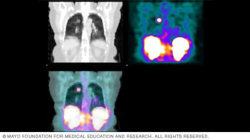

SPECT scan results

SPECT scan results can be in color or shades of gray. The varying shades or colors show which cells in the body are absorbing more or less of the radioactive tracer. This scan includes images of the kidneys, liver and spleen.

A radiologist or healthcare specialist with advanced training in nuclear medicine will study the results of your SPECT scan and send them to your healthcare team. Pictures from your scan may show colors that tell your team what areas of your body absorbed more of the radioactive tracer and which areas absorbed less. For instance, a brain SPECT image might show a lighter color where brain cells are less active and darker colors where brains cells are more active. Some SPECT images show shades of gray, rather than colors.